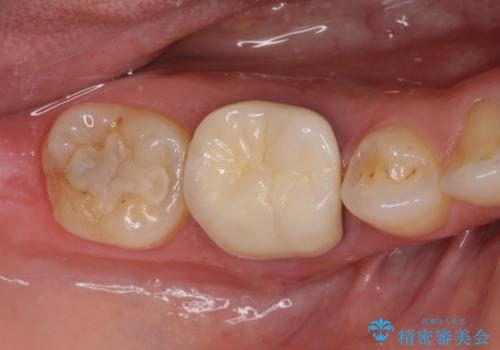

部分矯正を併用した奥歯のインプラント治療